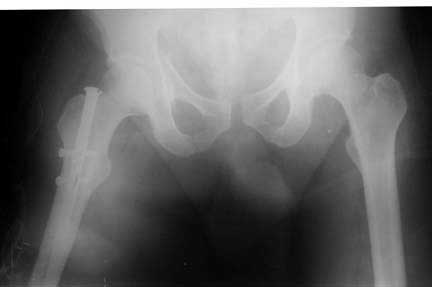

Middle aged male who was injured when a log of wood fell on him ina saw mill. Haemodynamically patient stable. No visceral injuries detected. The following musculoskeletal injuries detected: 1) Closed fracture femur. 2) Pubic symphysis disruption. 3) Right inf pubic rami fracture. 4) Right acetabular fracture. Head of femur located. 5) Right Sacroiliac joint anterior opening.

Your plan sounds fine. The acetabular fracture looks like a high ramus fracture that happens to enter the acetabulum. The CT scan is blurry, and you haven't provided any oblique views of the acetabulum - but my guess is that the 'tab is concentric.

The pelvic injury appears to be an APC1 (AP Compression) by the Young-Burgess classification.

Dalal, Young, Burgess and Siegal report a 9% incidence of GU injury with APC1.

Further pelvic AP compression by driving a fracture table perineal post against an injured perineum with possible urethral, bladder, rectal and/or pudendal nerve attenuation sounds risky.